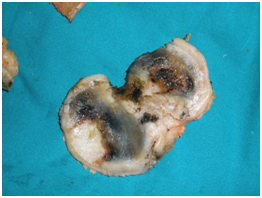

The patient was scheduled for surgery of total right knee arthroplasty. During the surgical approach of the knee we observed the dark pigmentation of the synovium, the bone cartilage, the quadriceps tendon and the menisci. This rare condition, characterized by many as ‘’Black Bone Disease’’, is accompanied by extensive destruction of the femoral condyles and the tibial Plateau due to arthritis. We performed a cemented total arthroplasty and sent pieces of the bones and the meniscus for histological examination (Figure 4).

Histological examination confirmed the clinical diagnosis. The disease is ochronotic arthropathy or alcaptonuria. The confirmation was enhanced by urine examination as well as by examination of pieces of the synovium, the meniscus and bone pieces of the knee (Figure 5) and synovial liquid (Figure 6). At the overview of the patient we detected dark pigmentation of sclera, which is characteristic of alcaptonuria (Figure 7).